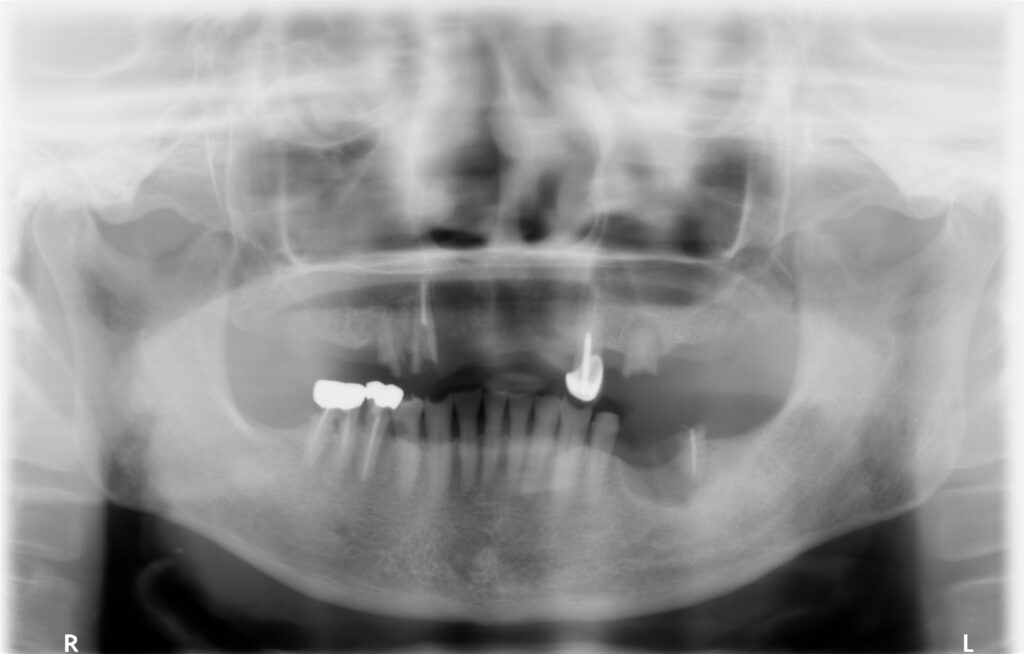

■治療前の状態

パノラマレントゲンから、上顎・下顎ともに残っている歯が少なく、噛み合わせのバランスも不安定な状態でした。

・上顎:3・3・4・6番のみ残存

・下顎:5・6・7番のみ残存

上顎は残っている歯の位置と本数が少なく、部分入れ歯の維持が不十分で、日常生活に支障が出ている状態でした。